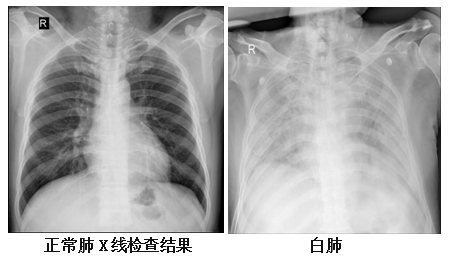

邵元伟介绍,健康的肺是由通气功能正常的肺泡组成,这样的肺泡充满了空气,在 X线和 CT 上都是透光的,显示为“黑色”。当肺部出现病变,如感染、水肿等,引起肺泡被渗出液及炎性细胞等充填,X线穿透肺泡的能力降低,在影像学上的表现就是出现白色区域。但并不是只要肺部出现了白色区域就都叫白肺。一般来讲,肺部炎症较重、渗出液较多,白色的影像区域达到双肺面积的70%—80%时,在临床上才会把它称为“白肺”,这是肺部影像学表现的一个口语化描述,目前主要涉及高龄的合并严重基础疾病的肺部感染患者,但占比非常低。